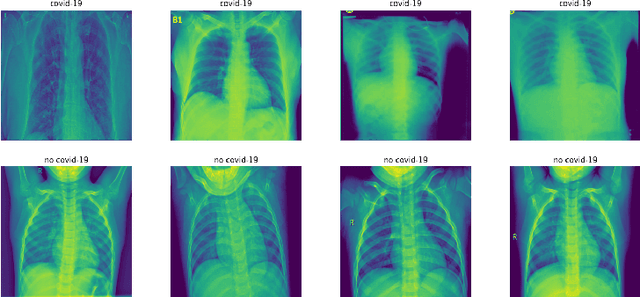

Abstract:With the recent outbreak of COVID-19, creating a means to stop it's spread and eventually develop a vaccine are the most important and challenging tasks that the scientific community is facing right now. The first step towards these goals is to correctly identify a patient that is infected with the virus. Our group applied an unsupervised machine learning technique to identify COVID-19 cases. This is an important topic as COVID-19 is a novel disease currently being studied in detail and our methodology has the potential to reveal important differences between it and other viral pneumonia. This could then, in turn, enable doctors to more confidently help each patient. Our experiments utilize Principal Component Analysis (PCA), t-distributed Stochastic Neighbor Embedding (t-SNE), and the recently developed Robust Continuous Clustering algorithm (RCC). We display the performance of RCC in identifying COVID-19 patients and its ability to compete with other unsupervised algorithms, namely K-Means++ (KM++). Using a COVID-19 Radiography dataset, we found that RCC outperformed KM++; we used the Adjusted Mutual Information Score (AMI) in order to measure the effectiveness of both algorithms. The AMI for the two and three class cases of KM++ were 0.0250 and 0.054, respectively. In comparison, RCC scored 0.5044 in the two class case and 0.267 in the three class case, clearly showing RCC as the superior algorithm. This not only opens new possible applications of RCC, but it could potentially aid in the creation of a new tool for COVID-19 identification.